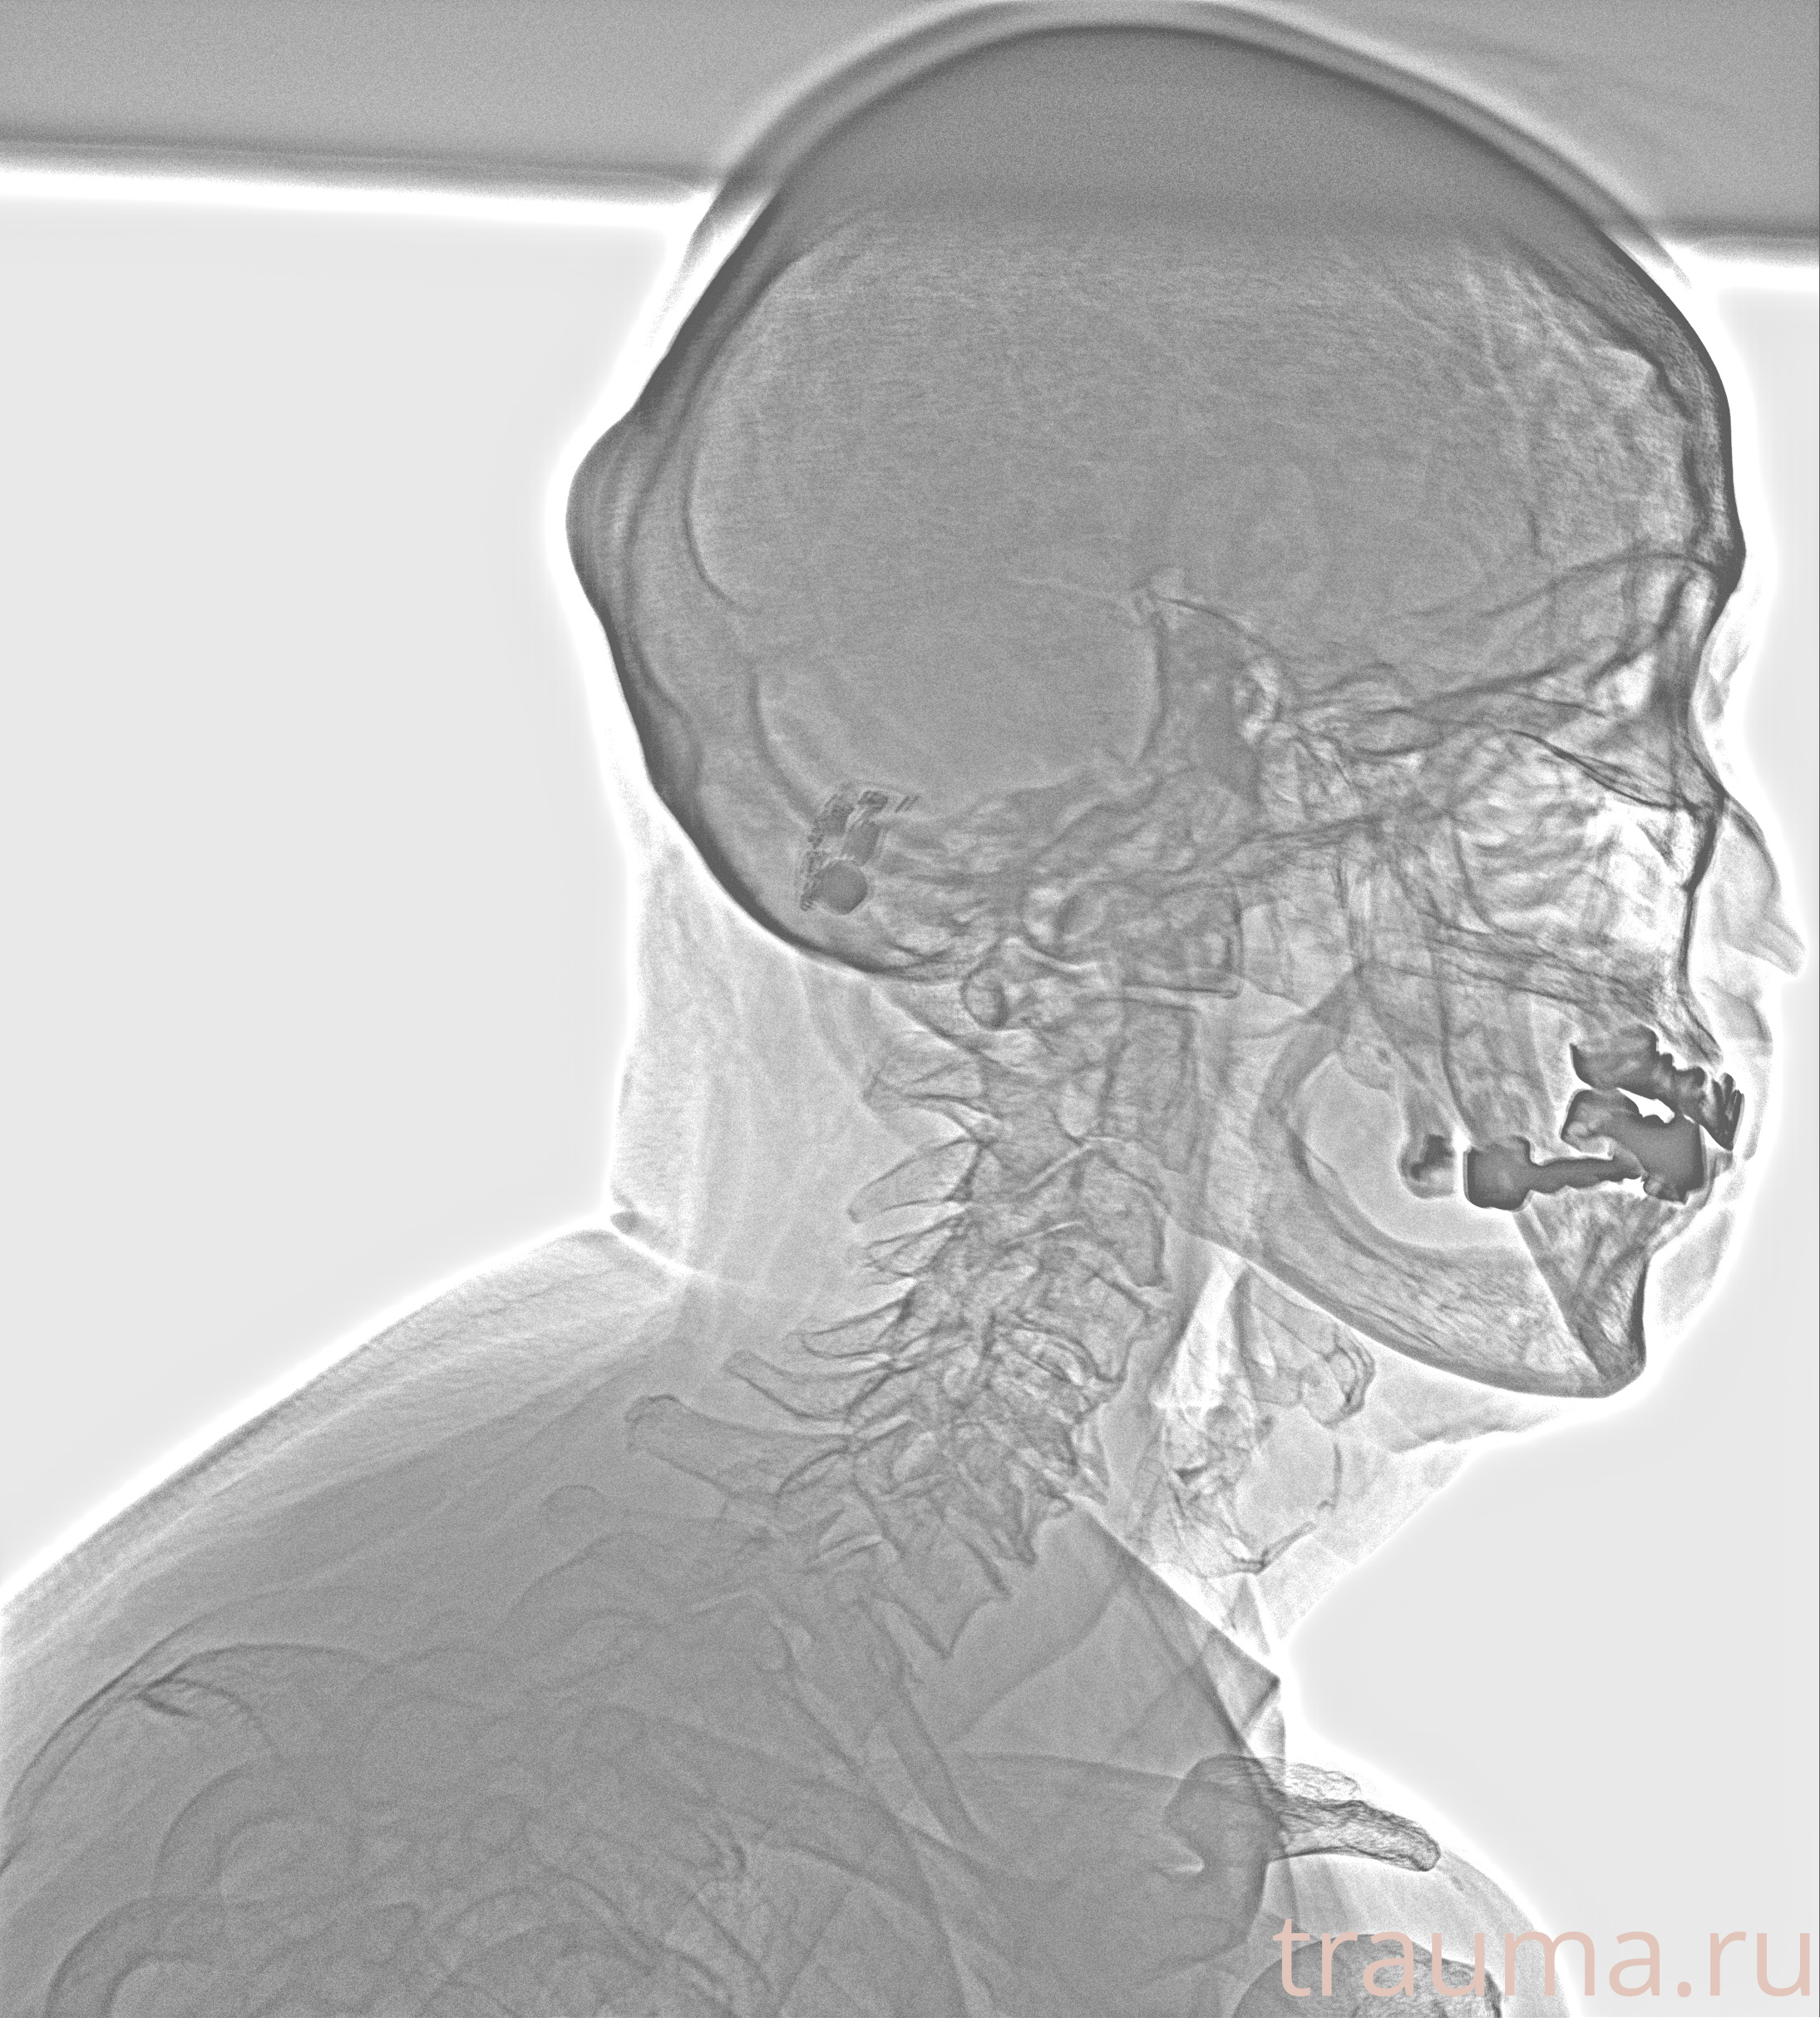

Рентген на дому: по вашему адресу приезжает врач-рентгенолог, травматолог-ортопед с мобильным рентгеновским аппаратом, проводит диагностику травмы или заболевания, делает необходимые рентгенограммы, дает рекомендации по дальнейшему лечению. Получить качественные снимки в домашних условиях возможно благодаря уникальной методике, разработанной МосРентген Центром для института  Склифосовского